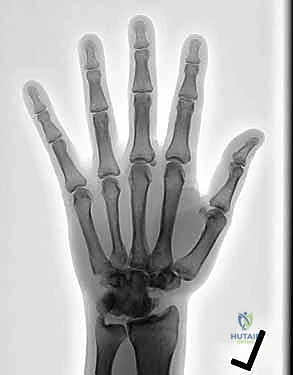

يُعد مفصل الرسغ تحفة هندسية بيولوجية، فهو أحد أكثر المفاصل تعقيدًا وديناميكية في جسم الإنسان. يتكون من شبكة معقدة من العظام الصغيرة والأربطة الدقيقة التي تعمل بتناغم مذهل لتوفير نطاق واسع من الحركة، المرونة، والقوة اللازمة لأداء كل شيء؛ بدءًا من الحركات الدقيقة كالكتابة وإمساك الإبرة، وصولاً إلى المهام الشاقة كحمل الأوزان واستخدام الأدوات الثقيلة.

ومع ذلك، فإن هذا التعقيد يجعله عرضة بشكل كبير للإصابات والأمراض التنكسية. يمكن أن تؤدي الكسور القديمة غير الملتئمة، وتمزقات الأربطة المهملة، أو أمراض مثل التهاب المفاصل الروماتويدي، إلى تآكل الغضاريف الناعمة التي تبطن نهايات العظام. عندما تتآكل هذه الغضاريف، تحتك العظام ببعضها البعض مباشرة، مما يولد آلامًا مزمنة، وتورمًا، وتيبسًا، وضعفًا شديدًا في قبضة اليد، وهو ما يؤثر بشكل كارثي على جودة حياة المريض وقدرته على الاستقلالية.

في المراحل المتقدمة من هذه الحالات، عندما تفشل العلاجات التحفظية في توفير الراحة، يبرز "تثبيت مفصل الرسغ الجزئي" كحل جراحي ذهبي. على عكس جراحات التثبيت الكلي التي تلغي حركة الرسغ تمامًا، فإن التثبيت الجزئي هو فن جراحي دقيق يهدف إلى استئصال أو دمج الأجزاء التالفة فقط، مع الحفاظ على الأجزاء السليمة لتعمل كآلية مفصلية جديدة.